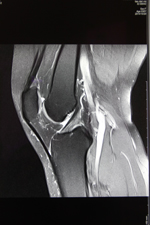

近期,我院今年新购的德国西门子MAGNETOM Avanto I-Class全身磁共振成像系统经过安装调适后正式投入使用。该系统为目前世界上最先进的1.5T磁共振,可以进行全身各部位的高质量扫描。该系统最突出的优势是:成像速度快、图像质量高,扫描覆盖范围大、扫描噪音小。患者在得到最快捷、最准确诊断的同时,还能享受到最舒适安静的检查。

该系统尤其在肿瘤诊断方面具有其突出的优势:一、个是分辨率好;二、反映的特性比较多,有利于临床把握肿瘤的诊断。三、它可以一次性的完成全身的核磁检查,第一次真正做到了高分辨的全身成像。可以很好的评估肿瘤的转移扩散程度,也通过全身的弥散成像使我们了解局部的淋巴结和全身的淋巴结,从其它医院完成的大量的病例来看,Avanto在全身肿瘤的筛查、评估方面准确性非常高。这为我院的肿瘤影像诊断提供了一个新的,有力的武器,为正常人进行磁共振全身疾病筛查带来福音。可真正做到对疾病早发现、早诊断、早治疗,使患者得到优质的医疗服务。